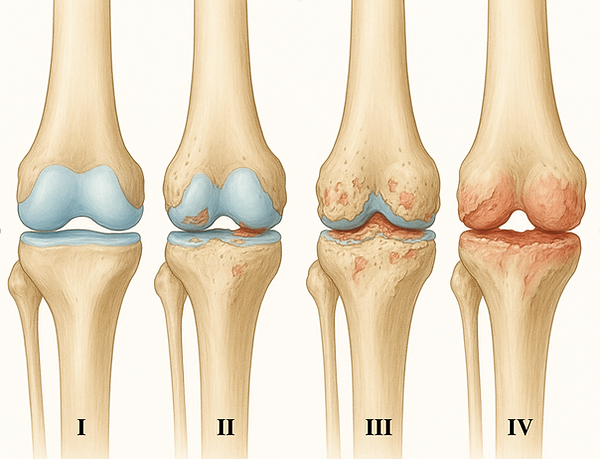

Voici les différents stades de l’arthrose :

Grade I : Cartilage ramolli, surface légèrement irrégulière (fibrillation débutante).

Grade II : Apparition de fissures superficielles et amincissement partiel du cartilage.

Grade III : Fissures profondes, cartilage très altéré atteignant presque l’os sous-jacent.

Grade IV : Usure et disparition complète du cartilage (ulcération), avec exposition de l’os sous-jacent